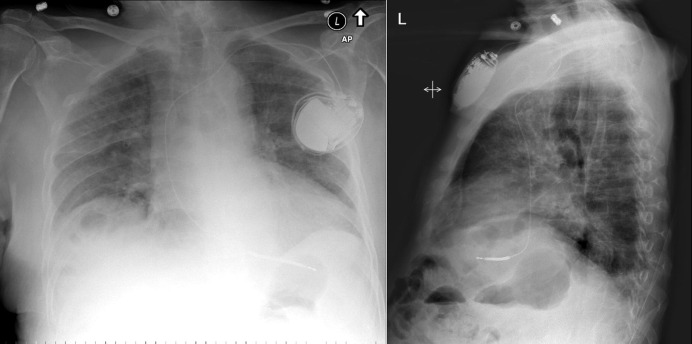

Figure 17-1

There is borderline cardiomegaly and definite calcification of a left ventricular aneurysm. There is increased pulmonary venous vascular prominence due to heart failure associated with the left ventricular aneurysm and systolic dysfunction.